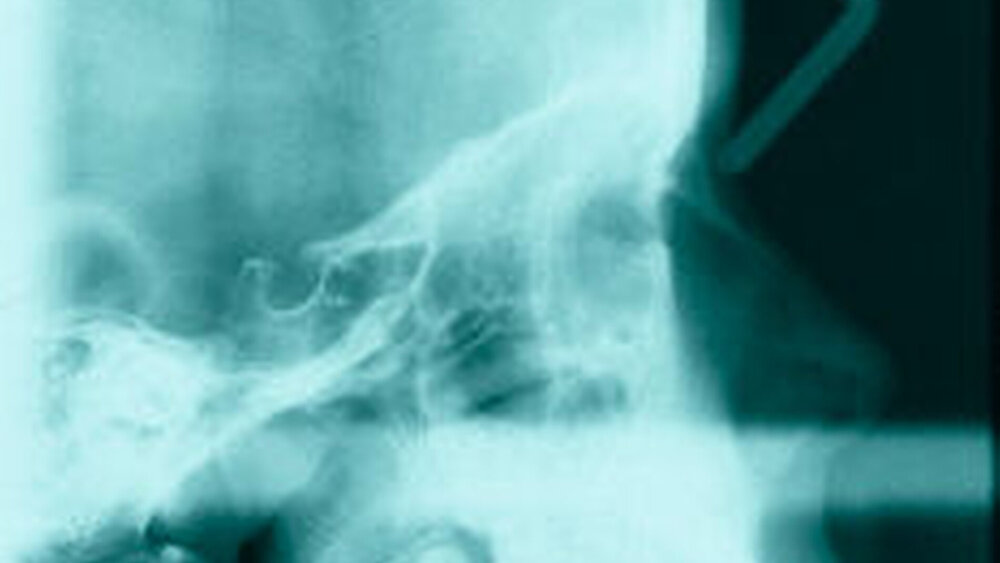

Bereits 2004 wies Carla Evans [Evans, 2005] auf das Risikomanagement bei Allgemeinerkrankungen hin und stellte am Beispiel der JIA dar, dass Unterkieferrücklagen und frontal offene Bisse aus der Kiefergelenkzerstörung entstehen können. Die Röntgenaufnahmen einer JIA-Patientin mit oligoartikulärer Form und Beteiligung des rechten Kiefergelenkes zeigen den typischen Verlauf sehr gut. Bei ursprünglich sehr dezenten Befunden, wie einer s-förmigen Mundöffnung von 44 mm, einer geringen Mittenabweichung um 2 mm nach rechts und einem frontal offenem Biss klagte sie über Schmerzen beim Essen, was den Anlass zur weiteren Diagnostik bot. Die erste Panoramaröntgenschichtaufnahme (Abbildung 1a-c) zeigt auf der rechten Seite einen abgeflachten Kondylus und eine bereits verstrichene Fossa condylaris. Ein Jahr später vermittelt das Fernröntgenseitenbild (Abbildung 1d) trotz fortschreitender kondylärer Resorption ein harmonisches Bild, während nach drei Jahren bei voranschreitendem Abbau des rechten Kondylus (Abbildung 1e) eine Rücklage der Mandibula und eine Bissöffnung manifest sind (Abbildung 1f).

Die Fernröntgenseitenaufnahme in Abbildung 2a zeigt ein „rheumatisches“ Profil mit retraler, hypoplastischer Mandibula, oft kombiniert mit einer Schwäche des M. masseter auf der betroffenen Seite. Der Funktionsschmerz erzeugt „Kaufaulheit“. Die Gesichtsasymmetrie (Abbildung 2b) betrifft meist Kinn, aufsteigenden Ast und die Höhe der Kieferwinkel. Auch die nicht dentoalveoläre Mittellinienverschiebung kann auf eine JIA hinweisen. Kreuzbisse variieren in Abhängigkeit vom Grad der Unterkiefermittenabweichung. Gemeinsame Auftreten eines frontal offenen Bisses und eines vergrößerten Overjet sind als klinische Anzeichen zu bewerten.